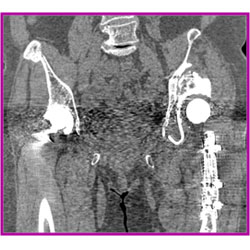

昨年10月にAuntMinnie(世界最大規模の放射線科情報ウェブサイト)よりBest New Radiology Softwareとして表彰を受けた逐次近似応用再構成である「iDose4 Premium Package」(アイドーズ フォー プレミアム パッケージ)を標準搭載し,低被ばくと高画質を高いレベルで実現。また金属アーチファクトを抑制する技術により,整形インプラント周辺の組織に対する視認性が高まり,診断をより効果的にサポートする。昨年北米放射線学会(RSNA2012)で発表をしたシステムモデル逐次近似再構成技術である「IMR」(アイエムアール)をオプション搭載することも可能。

「iDose4 Premium Package」なし |

「iDose4 Premium Package」あり |